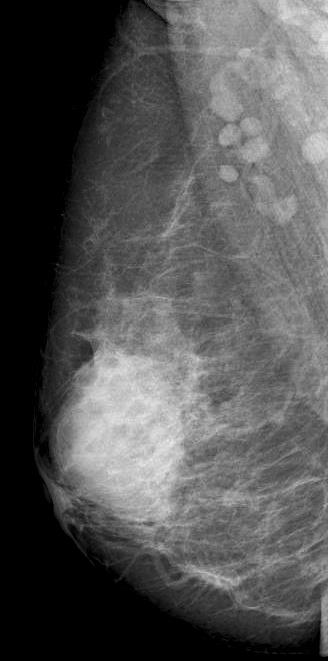

Diagnostic mammography showed scattered fibroglandular densities

Right breast showed in retroareolar region, an equal density oval mass with partially circumscribed margins measuring 6.6x5.2 cm. There were no associated suspicious calcifications. Right axilla showed a round dense LN of 1 cm.

Mammographic features include focal or global asymmetry, irregular focal mass, skin thickening with edema or trabecular thickening, asymmetric increased breast density and axillary lymphadenopathy. It can rarely present as a circumscribed mass or architectural distortion. Calcifications are very rare. Mammogram will be normal in about 8-45% of the cases in the setting of heterogeneously and extremely dense fibroglandular tissue.